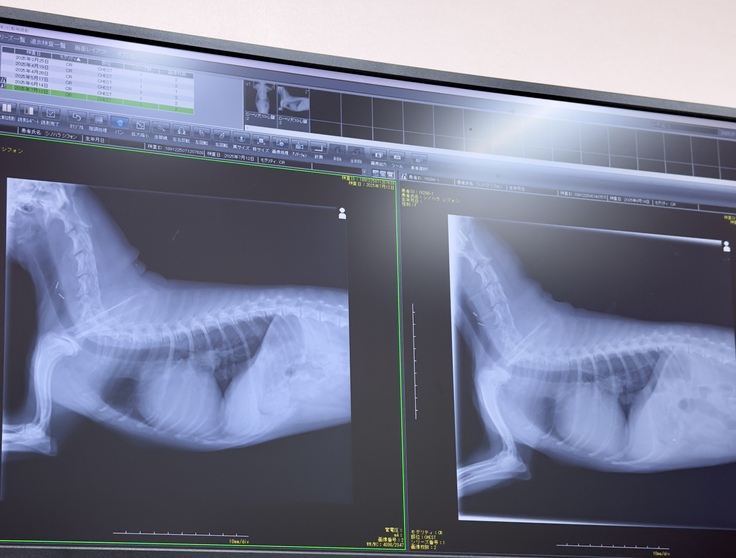

7月12日前回から4週間目、術後2ヶ月半となりました。

今日は検診日…猛暑の中シフォン頑張って検診に行って来ました。

結果は良好で手術をした左心房の方は完璧とのこと!

右心房の方の肥大と三尖弁の逆流が気になりそちらも検査して頂きました。

心臓自体の大きさは前回の6月14日の時と変わらずで右心房の肥大も然程なく三尖弁の不具合も今のところ気にならないとのこと。

血栓もなく順調だと言われ安心しました。